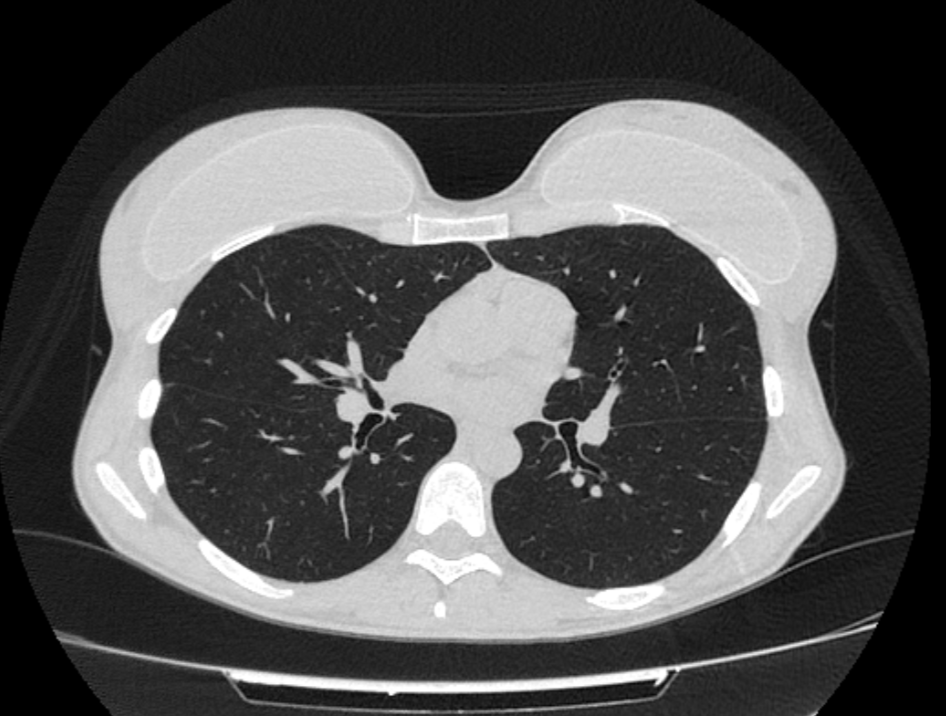

При проведении компьютерной томографии используется тот же принцип прохождения рентген-лучей через ткани с разными плотностями характеристиками. Правда при КТ лучи проходят в разных проекциях под разными углами, формируя множество срезов толщиной до 1 мм, и за счет чего формируется объемное изображение на экране и получается визуализировать мельчайшие патологические изменения. Также высокая четкость и объемность изображения формируется за счет техническими параметрами установок. Рентген-аппарат обладает коэффициентом ослабления в 20%, а КТ установка обладает коэффициентом в 0,5%

КТ и рентгенографию можно также делать с контрастированием для повышения степени детекции злокачественных новообразований и сосудов. Однако, при поиске таких патологий выбор очевиден в сторону КТ, за счет высокой степени визуализации и трехмерности изображения.